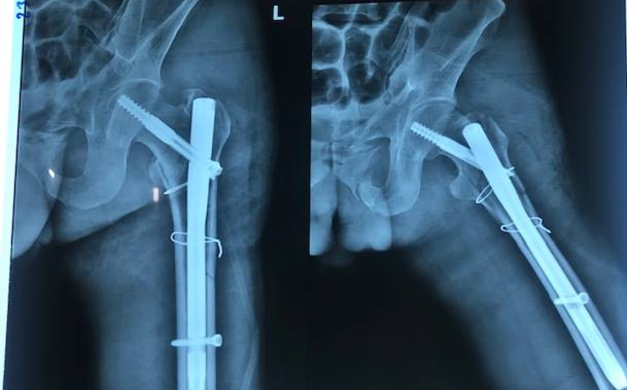

Anh Hiền ngã từ độ cao 8 m xuống đất khi thi công một công trình ở TP HCM, chấn thương nặng.